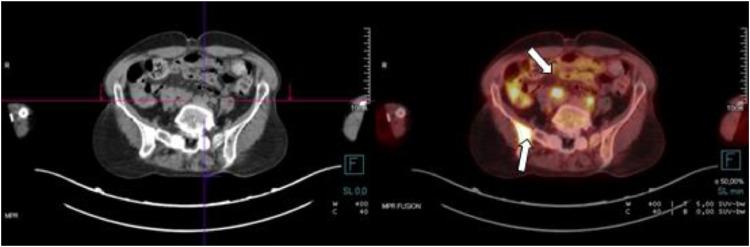

Osseous sarcoidosis is a rare manifestation of sarcoidosis, often mimicking other conditions like metastatic disease. Skeletal involvement occurs in only 3%-13% of cases (1), making diagnosis challenging. We present the case of a 63-year-old female with a 1-month history of inflammatory bone pain and multiple lytic and blastic lesions. A 63-year-old female presented with a 1-month history of inflammatory pain in the left hip and lumbar spine. Radiological studies, including magnetic resonance imaging (MRI) and computed tomography (CT), revealed multiple bone lesions throughout the lumbar spine, sacrum and iliac bones, raising suspicion of metastatic disease a bone biopsy confirmed a diagnosis of sarcoidosis. MRI and CT showed lytic and blastic lesions in the axial skeleton, with FDG-PET indicating diffuse uptake in the iliac bone and mediastinal adenopathy. Imaging was crucial in ruling out metastases and guiding the biopsy, which confirmed the diagnosis. Osseous sarcoidosis is a rare entity that poses a significant diagnostic challenge, often resembling metastatic disease. Imaging techniques such as MRI and CT, combined with biopsy, are effective, noninvasive methods for evaluation and diagnosis. The patient was treated with corticosteroids in high doses and systemic methotrexate, showing improvement in inflammatory pain and stabilization of the bone lesions.

骨结节病是结节病的一种罕见表现,常与转移性疾病等其他病症相似。骨骼受累仅见于3%-13%的病例(1),这使得诊断具有挑战性。我们报告一例63岁女性病例,其有1个月的炎性骨痛病史,伴有多发溶骨性和成骨性病变。一名63岁女性因左髋部和腰椎炎性疼痛1个月前来就诊。包括磁共振成像(MRI)和计算机断层扫描(CT)在内的影像学检查显示,整个腰椎、骶骨和髂骨有多个骨病变,这引发了对转移性疾病的怀疑,而骨活检确诊为结节病。MRI和CT显示中轴骨骼有溶骨性和成骨性病变,氟代脱氧葡萄糖正电子发射断层扫描(FDG-PET)显示髂骨有弥漫性摄取及纵隔淋巴结肿大。影像学检查在排除转移和指导活检方面至关重要,活检确诊了病情。骨结节病是一种罕见病症,带来重大诊断挑战,常类似转移性疾病。MRI和CT等影像学技术结合活检,是评估和诊断的有效、非侵入性方法。该患者接受了高剂量皮质类固醇和全身甲氨蝶呤治疗,炎性疼痛有所改善,骨病变稳定。